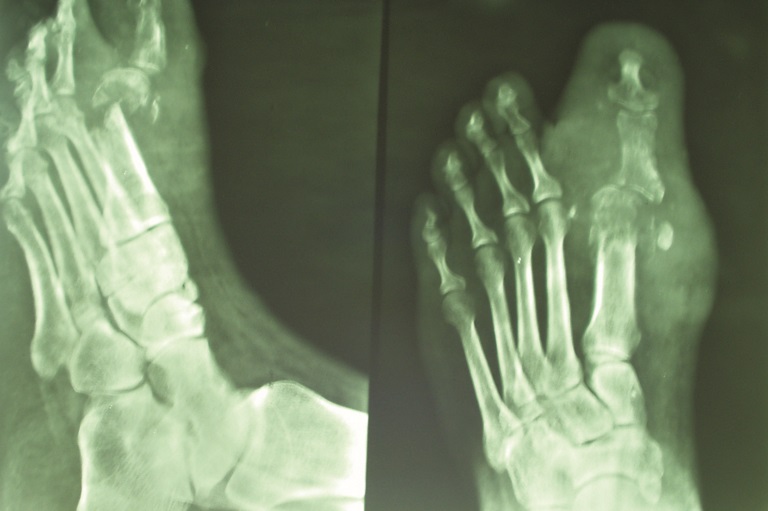

Typical hand deformities in cmt include intrinsic muscle wasting along with mcp hyperextension that limits finger flexion and impairs prehension. At this late stage the digits have been almost fully resorbed except for the index finger and the proximal remnant of the thumb. There is also a granulomatous inflammatory lesion located on the palmar surface.

Backgrounddisability assessment in leprosy patients is a very important factor in the evaluation of the effectiveness of a leprosy elimination program. An appropriate intervention is the zancolli lasso technique a procedure that has commonly been used to restore synchronous finger flexion to patients with lepromatous claw hands. Feet deformities planter ulcer foot drop inversion of the foot clawing of the toes absorption of the toes collapsed foot swollen foot and callosities.